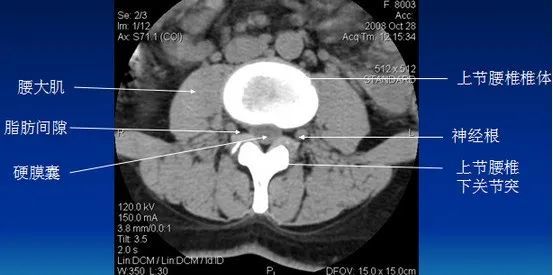

腰椎ct扫描层面及常见疾病的诊断附真实病例

腰椎ct扫描层面及常见疾病的诊断(附真实病例)